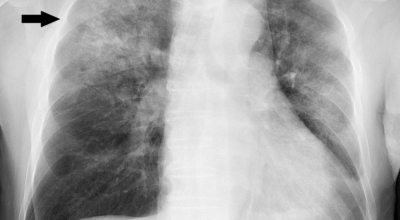

초기에 가벼운 기침으로 시작해 호흡하는 것조차 힘들어지게 되는데요 폐에 발생한 염증으로 인해서 폐의 신전성이 감소하고, 폐를 구성하는 폐포 세포가 망가져 적정 수준의 산소를 보관하지 못하기 때문에 호흡곤란이 유발될 수 있어요.

폐렴 증상 2. 천명음

폐렴으로 인해 기관지 협착이나 점액 증가하면서 기도가 좁아짐으로 인해 기도 저항이 세지면서 리듬성이 높고 휘파람 소리 같은 숨소리가 나옵니다. 천명음 같은 숨소리가 들린다면 폐렴 증상을 의심해 볼 수 있어요.